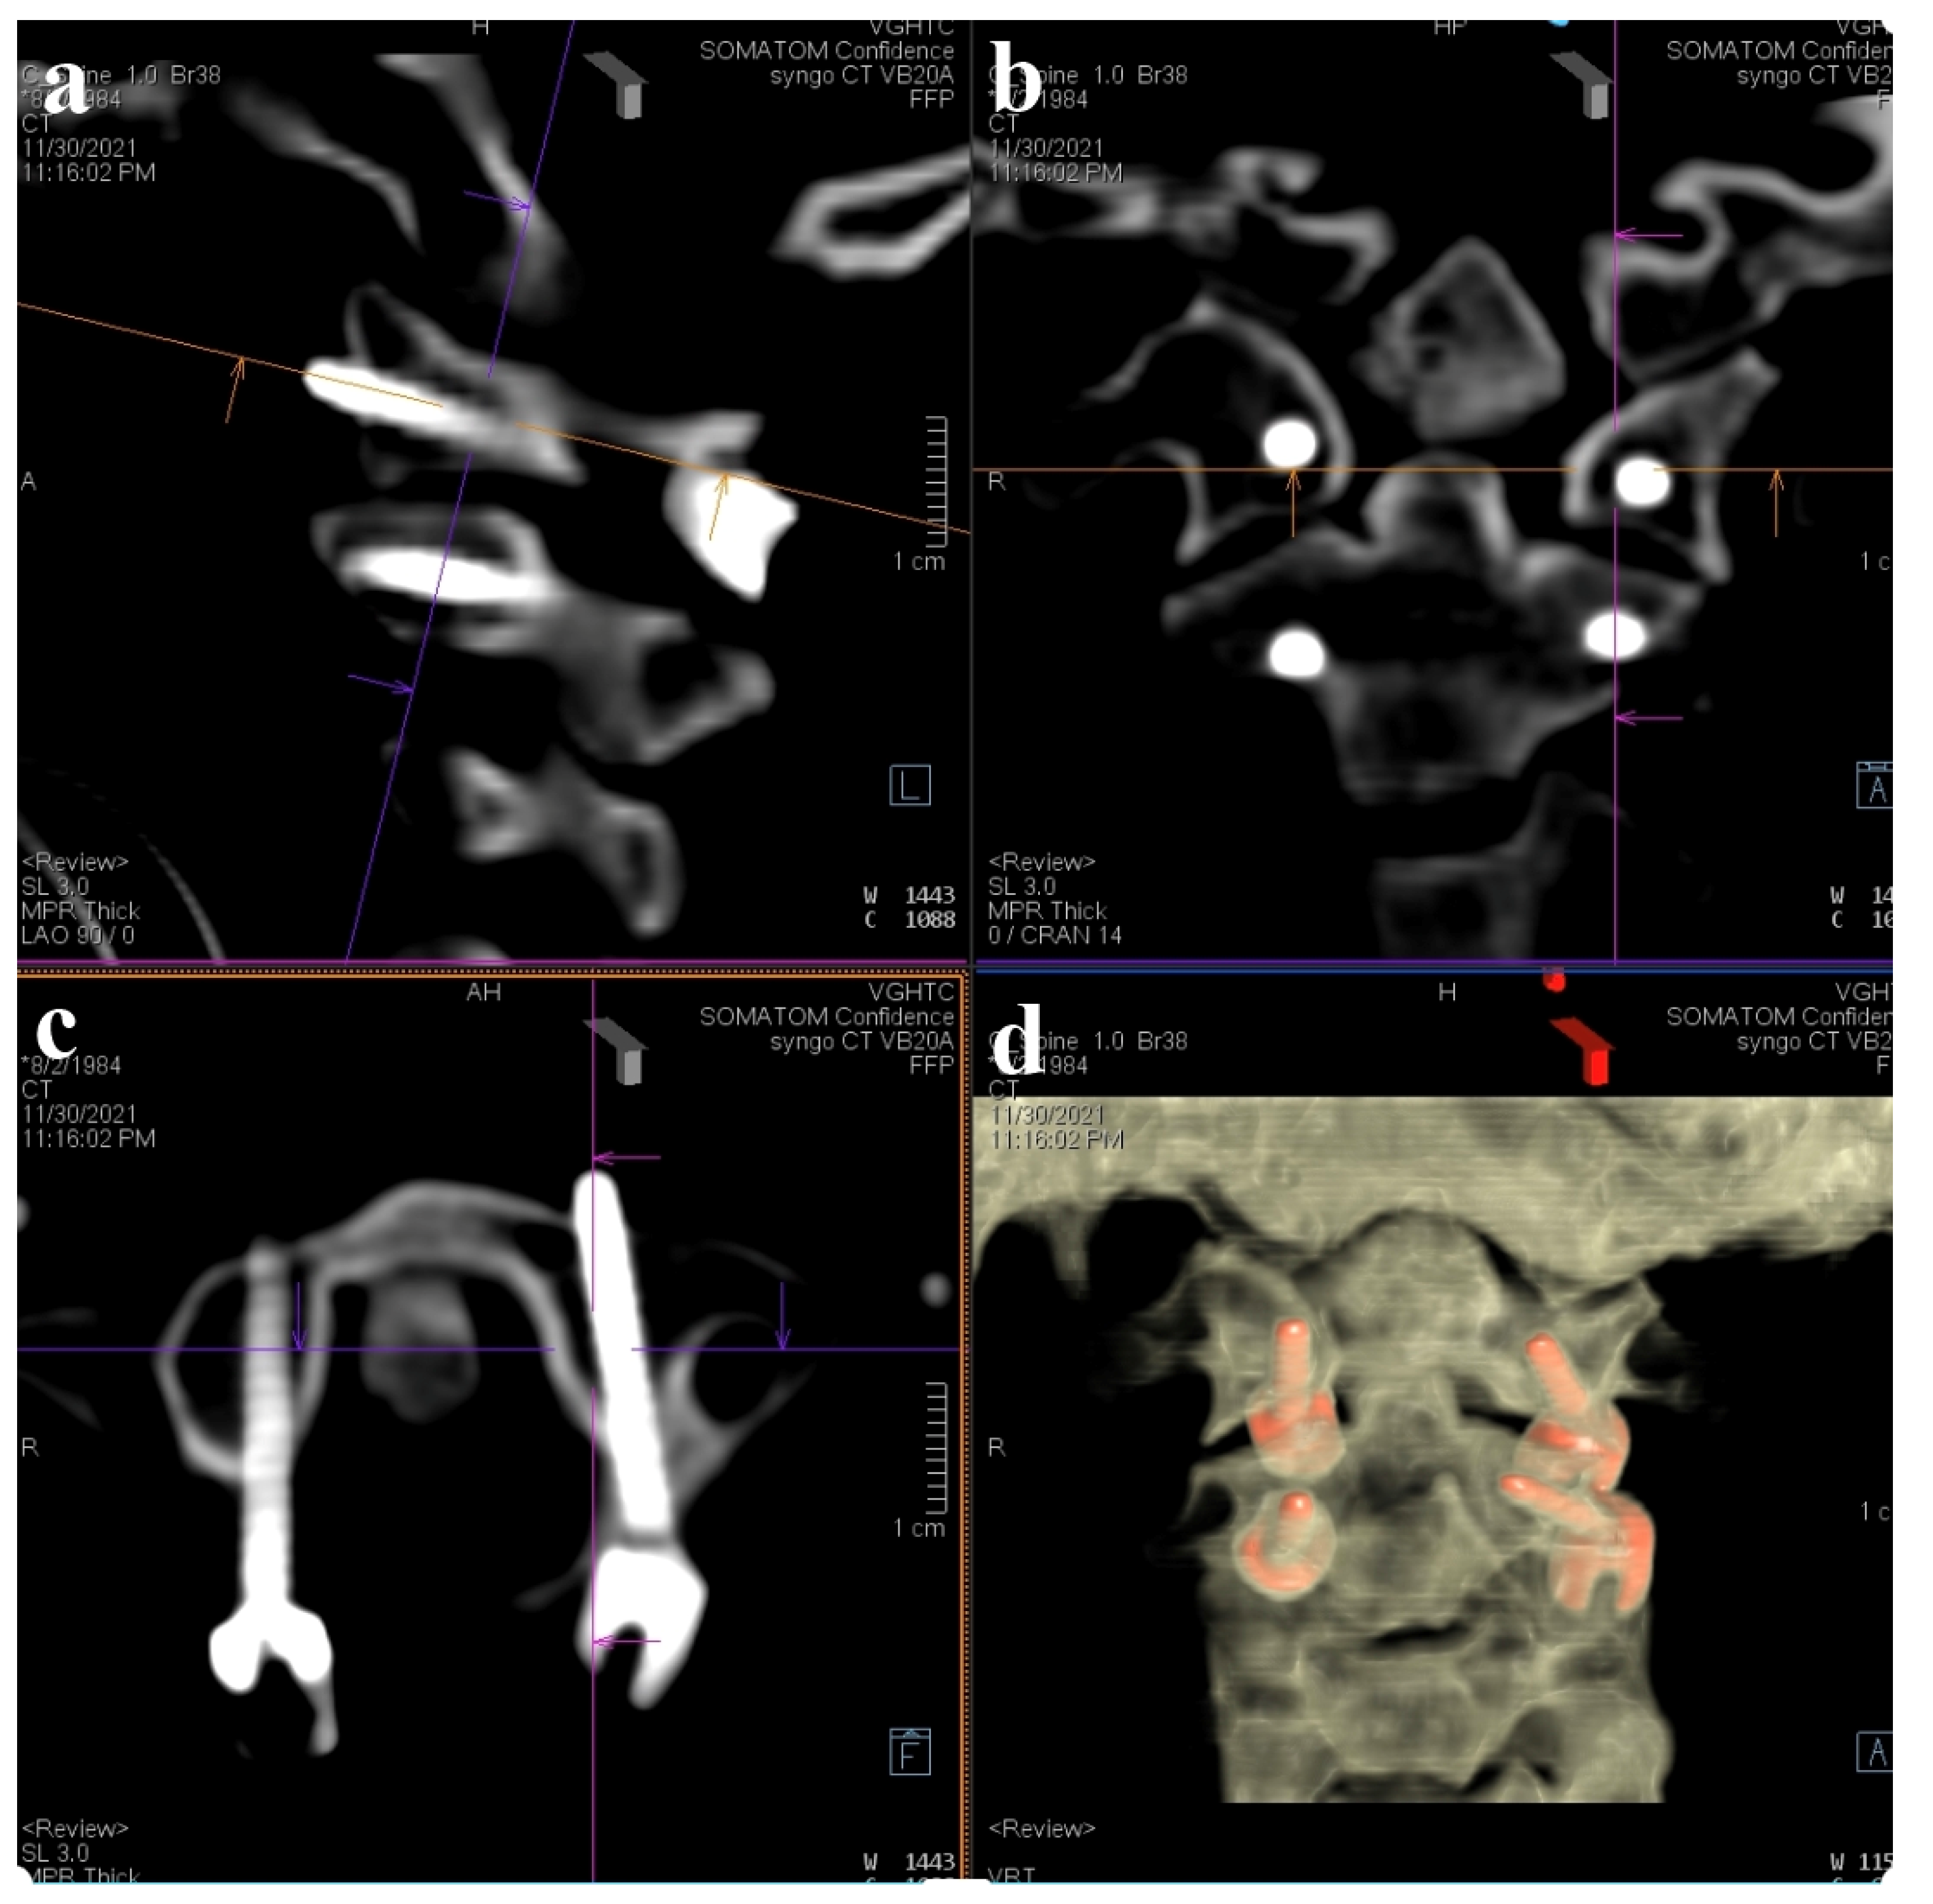

Preoperatively acquired cervical spinal MRI and CTA data were incorporated into the BrainLab Curve stereotactic neuro-navigation system (BrainLab AG, Munich, Germany). Prior to the procedure, we delineated the bilateral VAs and bony anatomy in distinct colors on a 3D-reconstruction derived from the preoperative CTA. At the surgery’s onset, the patient was secured in a prone position using a skull clamp. A navigation recognition reference cluster was affixed to the head frame for system registration. Subsequent to this, another stereotactic reference was attached to the KINEVO 900 microscope (Carl Zeiss AG, Oberkochen, Germany). An initial intraoperative CT scan was executed, and its imagery was coalesced with the pre-configured navigation images to counteract potential inaccuracies stemming from divergent scan positioning. For the C1-C2 fixation, we determined screw entry points and trajectories utilizing the navigation system, adopting a posterior midline technique. Initially, the lateral facet of the C1 posterior arch was unveiled to discern bilateral–lateral masses. Subsequent exposure included the spinous process, laminae, and the medial segments of C2 lateral masses. Utilizing the AR modality, the bilateral VAs, distinctly marked in red, were distinctly observed under the microscope. Concurrently, projections of the supplementary osseous structure were cast onto the operative field (Figure 4). Subsequently, entry points and trajectories for the C2 pedicular screws were orchestrated using real-time navigation in sync with the microscope-integrated AR system (Figure 5). Upon appropriate magnification and zooming out, the surgeon could clearly visualize the anatomical structures, avoiding any obstruction caused by surgical tools. Validation using AR navigation and intraoperative fluoroscopy confirmed the correct positioning. We proceeded by creating a pilot hole with a 2 mm high-speed burr. Following the pilot hole, we used a tool equipped with a navigator to ensure adequate bone purchase and a safe trajectory for further tapering. Finally, we placed poly-axial C2 pedicular screws (3.5 × 28 mm) along the pre-established trajectory, ensuring no breaches or vascular injuries. A corresponding navigation strategy was employed for the bilateral C1 lateral mass screws (3.5 × 30 mm). Post screw placement, an intraoperative CT scan affirmed the screw alignments (Figure 6). Succeeding surgical phases, encompassing the C1 laminectomy and rod application adhered to conventional protocols.

Figure 6. Intraoperative CT for screw validation. (a) Sagittal view; (b) coronal view; (c) axial view at C1 level; (d) reconstruction of 3D image.